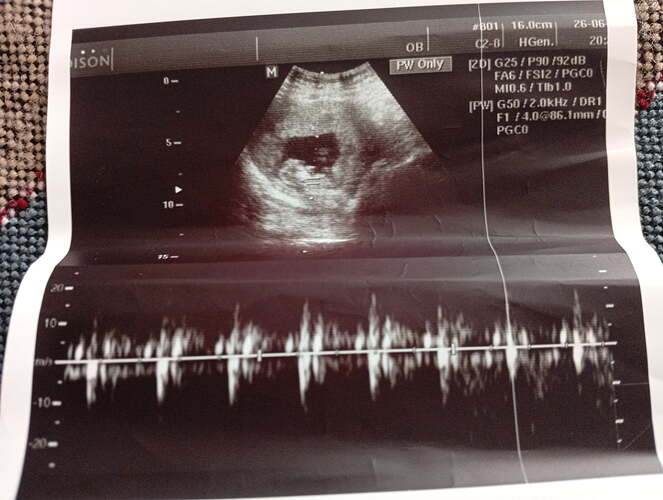

Ben kesenin fotosunu attım gözüküyor mu bilmiyorum sizce cinsiyeti bellimi

Kız gibi duruyor Allah sağlıkla kucağına almayı nasip etsin inşallah ![]()

Kız bu benim tahminim Hayırlı evlat olsun inşallah ![]()

Kız kesesi gibi duruyor sağlıkla gelsin ![]()

Sağlıcakla kucağına al canım. Bence erkek.

erkek gibi, sağlıkla gelsin bebişiniz.